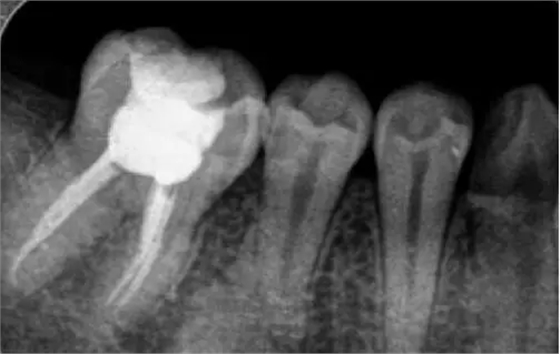

為什么根管治療需要拍多張片?

根管治療時(shí),拍牙片是必要的,并且至少要保證3張牙片。

第一張:在治療前,幫助醫(yī)生了解牙根的基本情況,如根管預(yù)備是否到位等,并制定計(jì)劃。

第二張:在治療中,幫助醫(yī)生了解治療情況,如根管預(yù)備是否到位等,并指定下一步的計(jì)劃。

第三張:在治療結(jié)束后,幫助判定根管填充質(zhì)量,發(fā)現(xiàn)問(wèn)題及時(shí)補(bǔ)救。